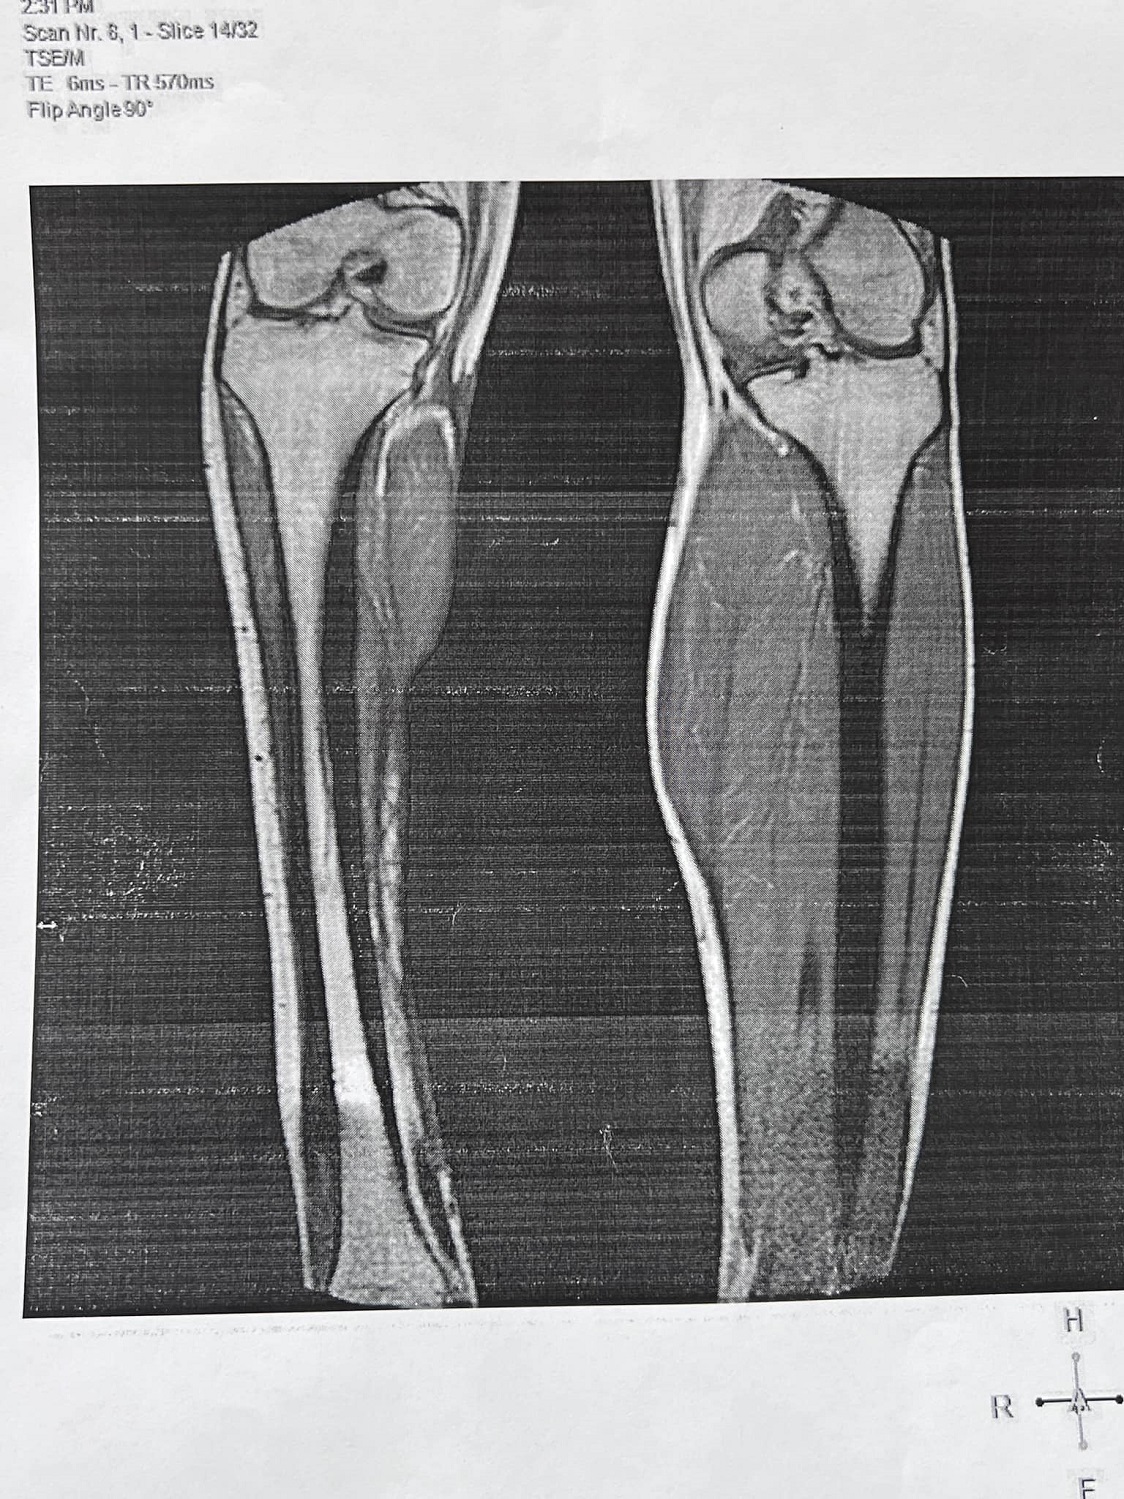

"Але наш харківський обласний МСЕК живе за власними законами Дай 3-4 тисячі доларів і буде тобі нормальне рішення. С*ки ви там! Заперечуватиму і домагатимуся того, що передбачено законом і совістю! Додаю фото ноги, бо бачу це поранення відчувається лише для мене", - написав він.

"Це так виглядає подяка людям, які стали на захист держави. Так тоді, виходить, треба було і загинути в одному зі штурмів. Це як слід ставитись до військових, що можна не брати до уваги висновки київських клінік, що права нога втратила свою функціональну здатність" та є біопротезом. Цього комісії МСЕК замало. 15 операцій. Замало. Треба вирвати все живе з людини і єхидно сказати: Якби була ампутація – то була б 2 група. Вимагаю звільнення Бунічевої Лариси Леонідівни з посади керівника обласної МСЕК", - написав військовий.